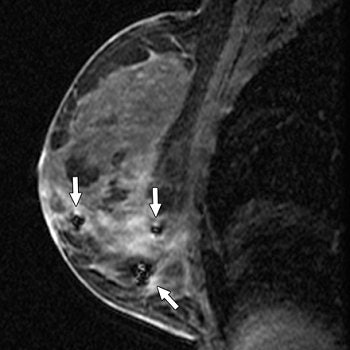

| A 63-year-old asymptomatic woman with family history of breast cancer who had abnormal right breast at MRI performed at outside facility. In sagittal T1-weighted contrast-enhanced image obtained after biopsy and clip placement at MRI-guided vacuum-assisted biopsy, lesion shows washout of contrast material, but no definite biopsy site changes are appreciated on this image. |

| Sagittal T1-weighted contrast-enhanced image after biopsy and clip placement shows signal void from marker in retroareolar region (arrow) in this image obtained during same sequence but just lateral to slice seen in top image. Histologic analysis of material obtained at MRI vacuum-assisted biopsy yielded benign breast parenchyma with dense stromal fibrosis, discordant with imaging. |